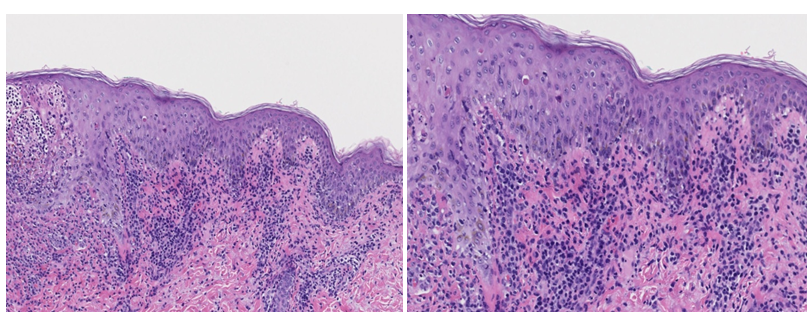

Skin examination revealed diffuse hemorrhagic vesiculopustules in different stages of healing involving the trunk, extremities, and face (Figure 1A)(Figure 1B). A skin punch biopsy from the right leg showed features of PLEVA with a lymphocytic infiltrate along the dermoepidermal junction, RBC extravasation, and epidermal necrotic keratinocytes. There was marked subepidermal edema with inflammatory cells and interface dermatitis, which extended down the hair follicle with intraepithelial apoptotic cells, but distinct herpetic viral cytopathy was not appreciated (Figure 2)(Figure 3). However, varicella-zoster virus (VZV) was detected by PCR from this skin site. The patient had elevated IgM titer to varicella, but no detected IgG antibodies to VZV. The patient was then diagnosed with primary varicella (chicken pox) and discharged on Valacyclovir 1gm TID for 7 days. At follow-up visit one-week later lesions were resolving.

Figure 2 C&D Higher power (10x & 20x) H&E section showing marked subepidermal edema with inflammatory cells extending down the hair follicle with interface dermatitis and apoptotic cells.

Figure 3 E&F Higher power (10x & 20x) H&E section showing an inflammatory lymphoid infiltrate at the dermoepidermal junction, dyskeratotic cells, and erythrocyte extravasation.